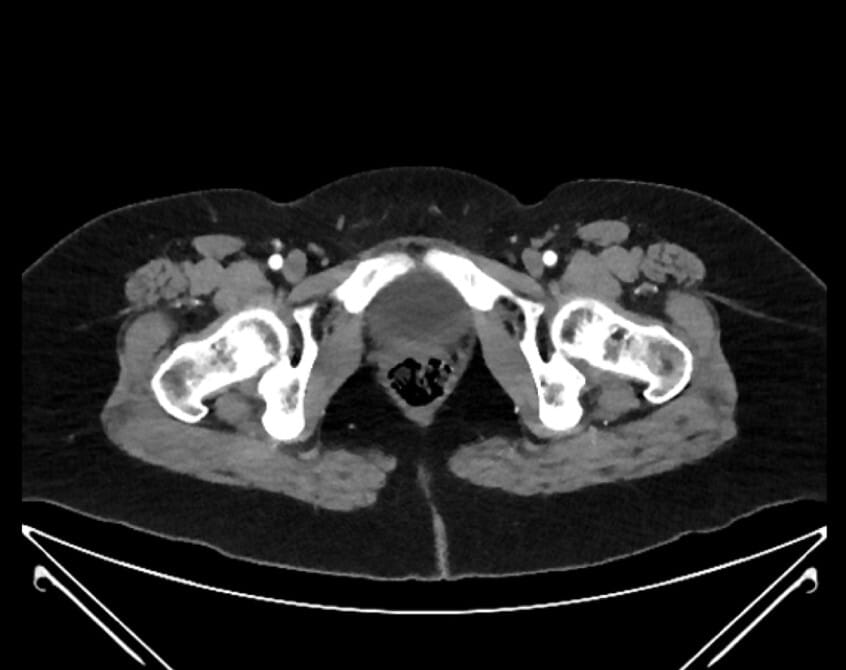

55. right common iliac artery

56. left common iliac vein

57. right common iliac vein

58. left common iliac artery

61. external iliac artery

62. iliolumbar artery

63. internal iliac artery

64. superior rectal artery

65. posterior division of internal iliac artery

66. anterior division of internal iliac artery

67. superior gluteal artery

68. inferior epigastric artery

69. deep circumflex iliac artery

70. inferior gluteal artery (off posterior division of IIA, variant)

71. obliterated umbilical artery

72. inferior epigastric artery

73. superficial circumflex iliac artery

74. aberrant obturator artery (off inferior epigastric artery, variant)

75. internal pudendal artery

76. common femoral artery